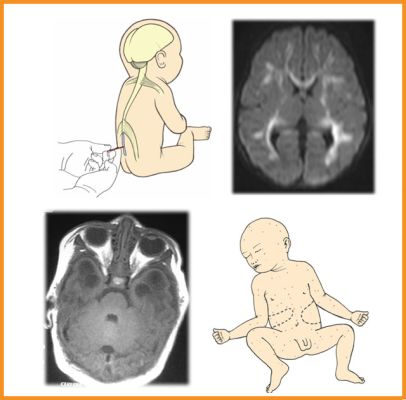

Infección del SNC

Cilla A, Megias G, Suarez J, Ojeda E, Cabrerizo M, Arnáez J. Human parechovirus and enterovirus in neonates: Distinct infections with overlapping features. Early Hum Dev. 2015;91:475-8.